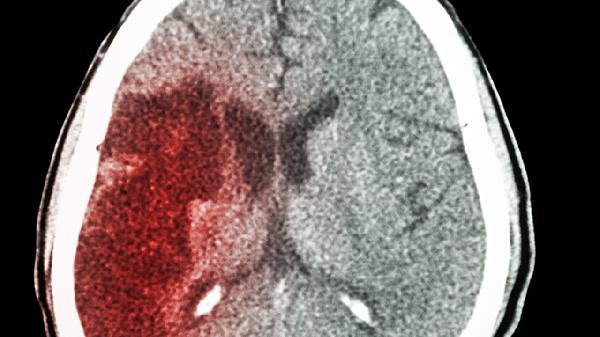

脑出血的饮食

脑出血患者饮食需以低盐、低脂、高蛋白、高膳食纤维为主,可适量食用西蓝花、燕麦、鲑鱼、鸡蛋、香蕉等食物,避免辛辣刺激及高胆固醇食品。饮食调整需结合患者吞咽功能及基础疾病情况,必要时在医生或营养师指导下进行。